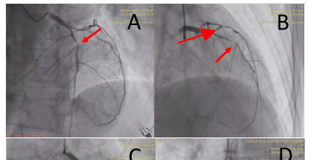

Cá thể hóa điều trị chống đông trong nhồi máu cơ...

PGS.TS. BS. HỒ ANH BÌNH*, TS.BS. HOÀNG VĂN**

TS.BS. ĐẶNG DUY PHƯƠNG***, ThS.BS. TRẦN QUỐC BẢO****

(*) Giám đốc Trung tâm Tim mạch, BV Trung ương Huế

(**) Phó Giám đốc Bệnh viện Tim Hà Nội

(***) Viện Tim TP Hồ Chí Minh

(****) Trung tâm Tim mạch, BV Trung ương Huế

Bệnh nhân cao tuổi mắc...